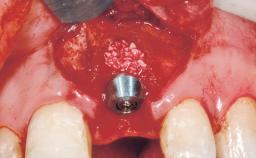

Late Placement of an Implant in a Maxillary Left Central Incisor Site

A 36-year-old female patient was referred for the replacement of the upper left central incisor (tooth 21), which had fractured. Although the tooth had been asymptomatic for many years, the crown began to loosen, at which time she presented to her dentist for an assessment. Teeth 21 and 22 had both been endodontically treated many years previously. She was a healthy individual and a non-smoker.

| Bone Augmentation | Horizontal|Staged |

| Bone Volume | Deficient horizontally, requiring prior grafting |